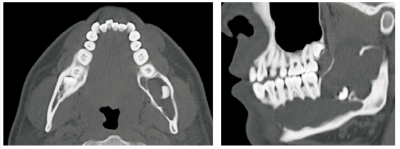

21 歳の男性。下顎左側部の腫脹を主訴として来院した。6か月前に気付き、徐々に増大してきたという。腫脹部に羊皮紙様感を触知する。検査の結果、開窓術を行うこととした。初診時の口腔内写真、エックス線画像、CT及び生検時の H-E 染色病理組織像を別に示す。